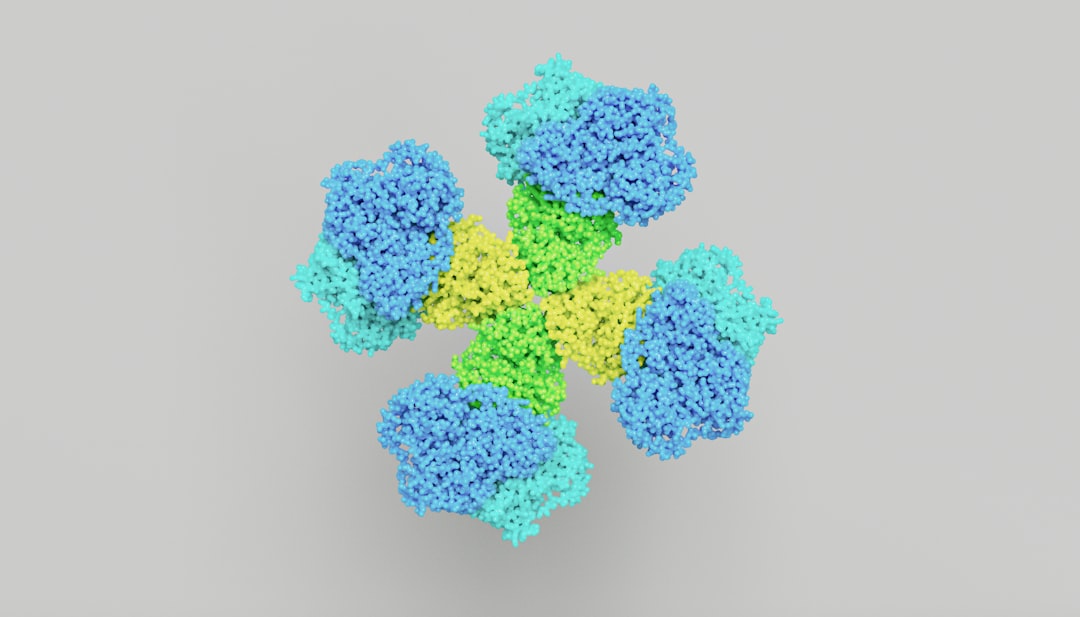

At its core, the idea of mirror proteins draws inspiration from nature’s own masterful designs. Biological systems are replete with proteins that exhibit remarkable stability and specific binding capabilities. Mirror proteins aim to replicate these characteristics through synthetic means, creating molecules that can non-covalently interact with and protect the API.

The term “mirror protein” alludes to the potential for these synthetic molecules to interact with their target API in a manner analogous to how a natural protein might bind to its natural ligand. However, it’s crucial to understand that these are not necessarily exact structural replicas in the literal sense of being left-handed or right-handed enantiomers. Rather, they are designed to possess complementary surfaces and binding pockets that can snugly embrace the API.

The power of most biological interactions lies in their specificity. Enzymes bind to substrates, antibodies bind to antigens, and receptors bind to signaling molecules with exquisite precision. Mirror proteins strive to achieve this same level of specificity, ensuring that they interact only with the intended API and not with other components of a formulation or biological system. This selectivity is paramount to avoid unintended side effects or loss of API function due to off-target binding.

Biologic drugs, such as therapeutic proteins and monoclonal antibodies, are notoriously fragile. They are prone to aggregation and denaturation, which can lead to a loss of efficacy and immunogenicity. Mirror proteins offer a promising avenue for stabilizing these complex molecules, enabling them to withstand the rigors of manufacturing, storage, and administration. Imagine making these delicate biological machines more robust and enduring.